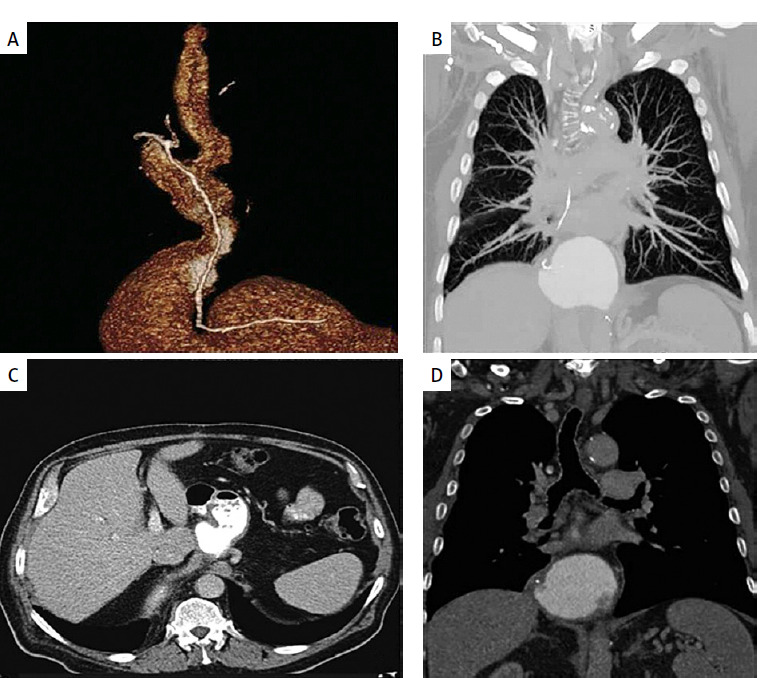

Abstract Image